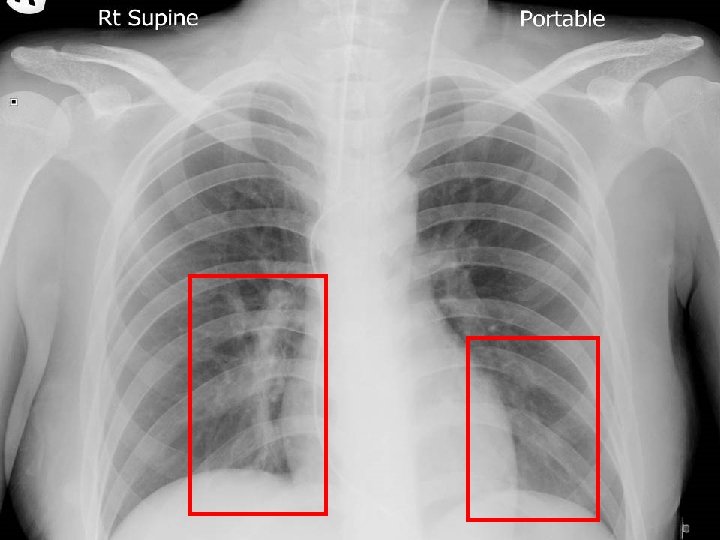

CMC ICU admission 27 th Aug GCS E 2 Vt. M 1 n Under sedation of Dormicum/ fentanyl n Pulse rate 90 sinus, not pacing dependent n Minimal motor response to pain for limbs n Lines not inflamed and CXR clear n Eye OT not available on same day n ? Primary sepsis foci n

Unexpected problems (1) TSH <0. 01 and T 4 30. 4 n Carbimazole 10 mg BD + inderal 10 mg tds since 10 th Aug to 14 th Aug n Complete heart block on 15 th Aug temp pacing at CCU on 16 th Aug n Sputum retention and respiratory failure intubated at ICU on 17 th Aug n Started Sulperazon + Amikacin for HAP n

Unexpected problems (2) Weaned off ventilator since 21 st Aug n Fever 40 degree + unconscious 25 th Aug resume ventilator support n Change pacing wire to LIJV n Stop Sulperazon and Amikacin change to Cloxacillin (ETA grew MSSA 24 th Aug) n EEG generalized encephalopathy n

Brain was so ill, but no answer…. Condition since 4 th September 2010 n Multi-focal inflammatory change over bilateral basal ganglia/ thalamus/ temporal lobes and brainstem on MRI, unlikely due to bacterial infection n GCS E 4 Vt. M 1 and all limbs flaccid n Persistent high fever and tachycardia despite Vanco/netro/fluconazole 14 days